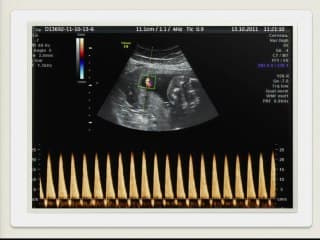

Le Dr Romain Favre expose le taux de complications dans les transfusions in utero (TIU) dans son secteur sur une période allant de 2000 à 2016.103 TIU, 6 opérateurs, 46 foetus.Les complications sont représentées par : le décès dans les suites du geste, les césariennes en urgences dans les suites du geste, le taux d'accouchement prématuré dans la semaine qui suit le geste, la rupture prématurée des membranes dans les 15 jours, chorioamniotite.L'AG moyen de la 1ère TIU est 27 SA avec parfois dès 20SA. 6 décès autour du geste. 9 complications dont 6 MFIU.Ce qui distingue les "morts" des "vivants" c'est la précocité du recours à la TIUCe qui distingue les TIU simples de celles qui sont suivies de complications, c'est la encore la précocité de la 1ère TIU.En conclusion depuis 2004 et l'avènement de la mesure du Pic Systolique de Vélocité (PSV) sur l'Artère Cérébrale Moyenne (ACM)Le nombre de recours à la TIU est moins fréquent avec pour conséquence une diminution du nombre de praticiens formés à ce geste et performants.